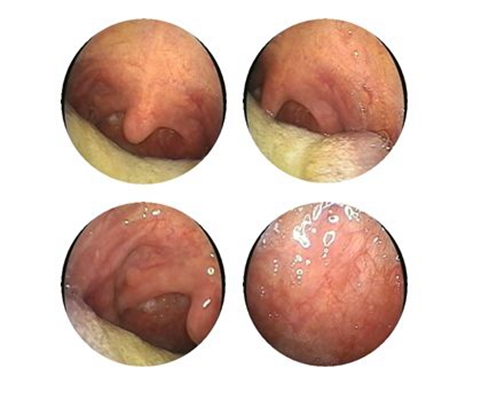

慢性咽喉炎圖片

喉部淋巴濾泡增生 (47)